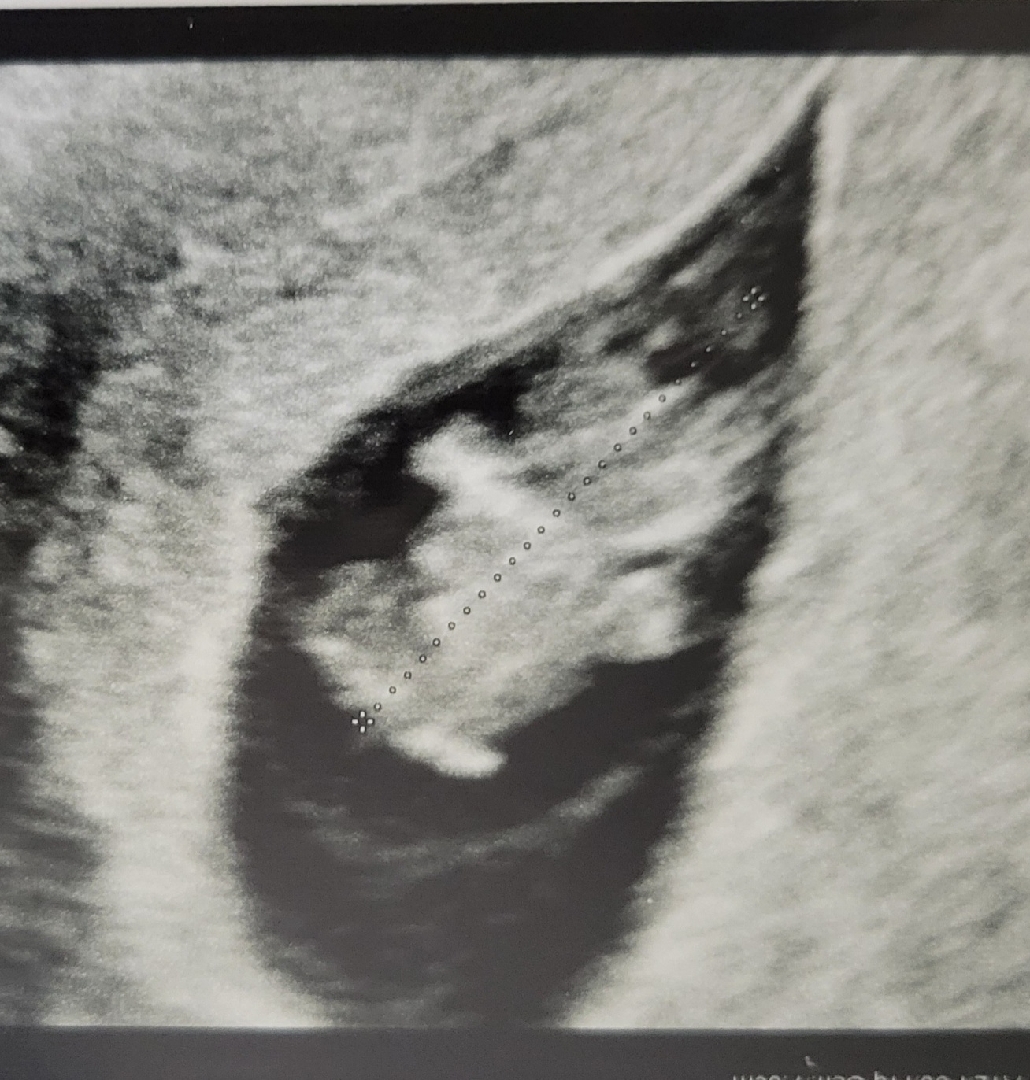

불안했던 7주 유산을 지나 드디어 하리보 보고왔어요 ㅜㅡㅜ

축하드려요! 손발이 아주 옹골지게 나왔어요~~ 건강한 아이로 자랄거 같아요 🥰